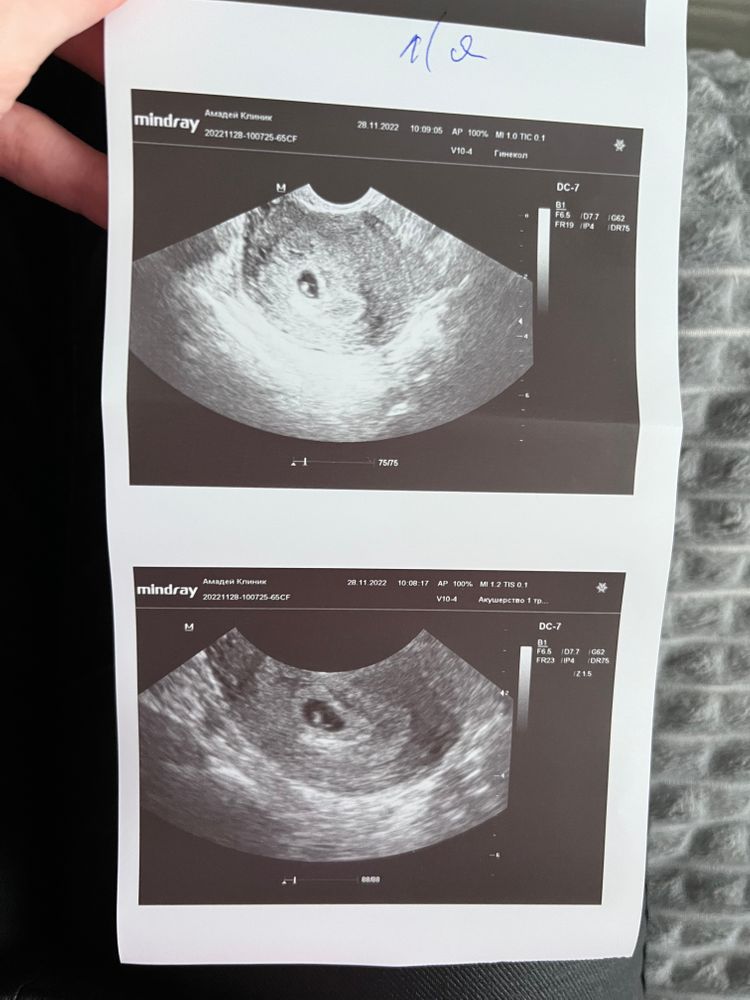

Узи в 6+5 Нед.

Сходила на узи . Нашли эмбрион , сердцебиение. Единственное, отстает по узи на несколько дней . Надеюсь, все будет хорошо 🤞🏼